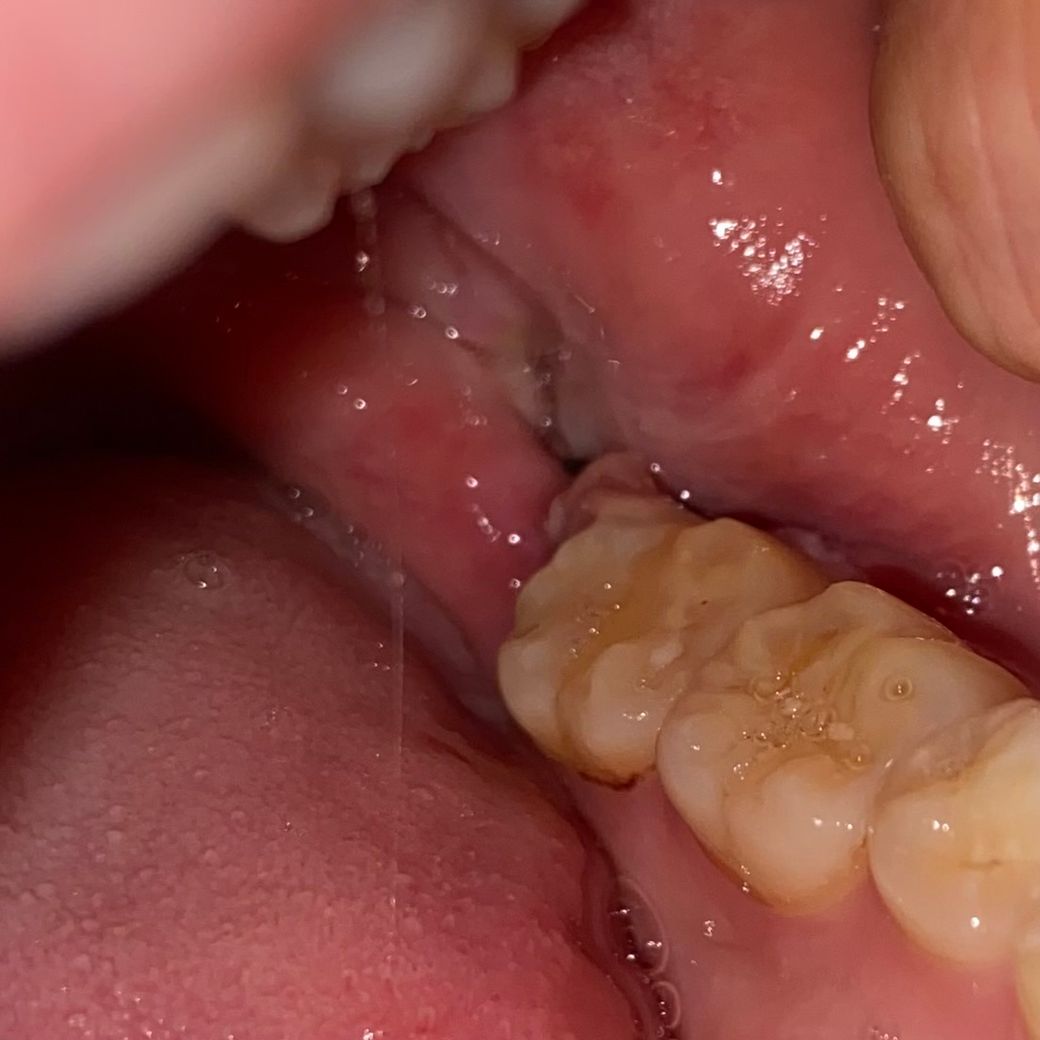

• 2번 째 사진

지난주 토요일에 발치했고 마지막 사진이 현재입니다 잘 낫고있는지 궁금해요... 어제 소독은 받았습니다. 근데 꼬맨 부분이 좀 땡기는데 이것도 맞나요